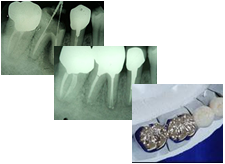

C3の治療法・症状

むし歯が歯の神経(歯髄)まで進行しています。歯の痛みをかなり感じる状態です。以前に治療を受け神経を抜いてしまった人や、むし歯が進行して神経が死んでしまった状態です。

治療法

むし歯に犯された部分を完全に削り取り、歯髄を消毒します。削った部分を被せ物がしやすいように形を整えたり土台を入れます。後日被せ物が完成したら来院し歯と被せ物を接着剤で固定します。